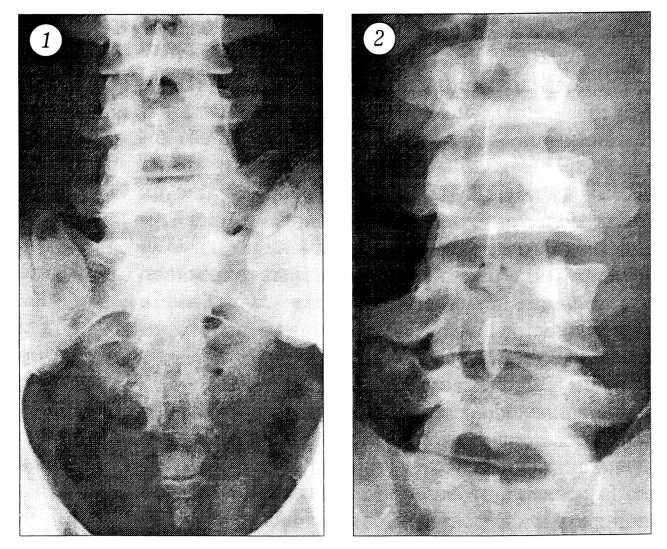

При рентгенологическом обследовании поперечно-крестцовый неоартроз (между поперечным отростком L5 позвонка и крестцом — рис. 1) обнаружен у 12 (70,6%) больных, попе-

речно-подвздошный (между поперечным отростком L5 позвонка и подвздошной костью) — у 4 (23,5%), поперечно-поперечный (между поперечными отростками L4 и L5 позвонков — рис. 2) — у 1 (5,9%) больного. Рентгенологическая картина неоартрозов поперечных отростков характеризовалась наличием субхондрального склероза сочленяющихся поверхностей и узкой, местами неравномерной суставной щелью.

Рис. 1. 1. Поперечно-крестцовый неоартроз. 2. Поперечно-поперечный неоартроз (между правыми поперечными отростками L4 и L5 позвонков).